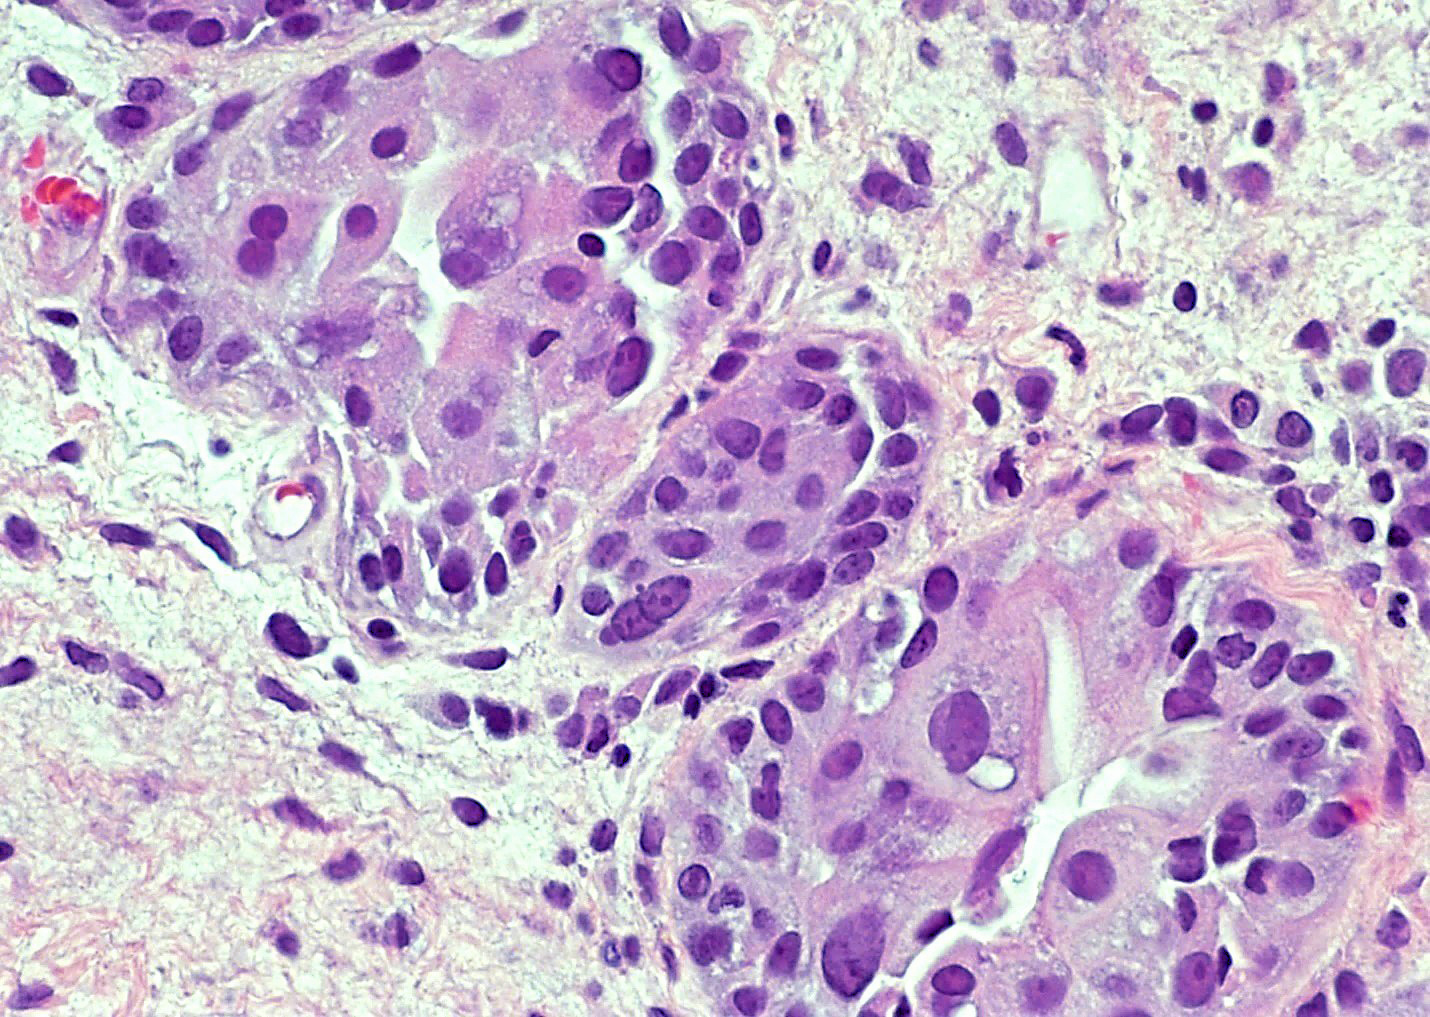

Microscopic (histologic) description

- Vessels with fibrin thrombi, fibrinoid vascular necrosis, vascular congestion, thickened walls, endothelial proliferation and telangiectasia

- Acute and chronic inflammation

- Reactive multinucleated stromal fibroblasts with smudgy nuclei

- Fibrosis and edema

- Hemorrhage and hemosiderin

- Urothelium can show

- Nuclei with variation in nuclear size and shape, hyperchromasia, vesicular or smudgy chromatin

- Eosinophilic or amphophilic cytoplasm, cytoplasmic vacuoles

- Multinucleated giant cells (Am J Surg Pathol 2008;32:92)

- Usually no mitotic figures

- Surface erosion, ulceration

- Squamous metaplasia

- Pseudocarcinomatous urothelial hyperplasia: variable sized urothelial cords and nests with rounded or irregular edges present in the lamina propria and enclose dilated blood vessels with fibrin deposition (Am J Surg Pathol 2008;32:92)

- Acute phase: edematous, congested and telangiectatic vessels, acute and chronic inflammatory infiltrate, atypical stromal cells with multinucleated forms

- Chronic phase: atrophic urothelium, atrophic smooth muscle layer, collagen deposition (fibrosis) (Am J Surg Pathol 2004;28:909)

Microscopic (histologic) images

Contributed by Y. Albert Yeh, M.D., Ph.D. and Jennifer Lee, M.D.

Sample pathology report

- Urinary bladder, right wall polypoid lesion, transurethral resection:

- Radiation cystitis with pseudocarcinomatous urothelial hyperplasia (see comment)

- Muscularis propria not identified

- Comment: There is a history of radiation therapy per the medical record. The transurethral resection of the bladder lesion shows fragments of urothelial mucosa with total and partial denudation of urothelium. The urothelial lining cells show reactive changes. There is marked edema, hemorrhage and mixed inflammatory infiltrate composed predominantly of neutrophils and lymphocytes in the lamina propria. Reactive multinucleated stromal fibroblasts are seen. Telangiectatic vessels with fibrinoid necrosis and intravascular fibrin deposition are seen. Anastomosing cords and nests of urothelial cells encircling the vessels with fibrin deposition is evident. Urothelial cells with hyperchromatic nuclei, increased nuclear to cytoplasmic ratio and prominent nucleoli are seen. These features are consistent with radiation cystitis with pseudocarcinomatous urothelial hyperplasia. Muscularis propria is not identified in this specimen.

Board review style question #1

A 68 year old man presented with hematuria and dysuria. He has a medical history of prostate cancer that was treated with radiation therapy. Cystoscopy revealed hemorrhage in the right bladder wall. A transurethral resection of the lesion was performed. A photomicrograph is shown above. What is the diagnosis?

- Cystitis cystica

- Invasive urothelial carcinoma, nested variant

- Radiation cystitis with pseudocarcinomatous hyperplasia

- Urothelial carcinoma in situ

Board review style answer #1

C. Radiation cystitis with pseudocarcinomatous hyperplasia. Answers A, B and D are incorrect because anastomosing cords and nests of urothelial cells encircling ectatic vessels with intravascular and stromal fibrin deposition in a background of mixed inflammation are not present in these entities.